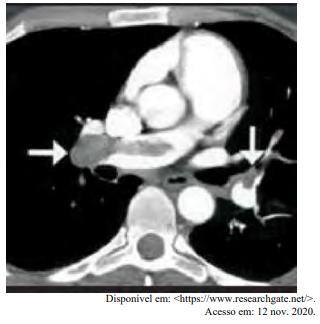

Certa idosa de 70 anos de idade é levada ao consultório médico por familiares, com relato de dor no peito há oito horas. Quanto a comorbidades, ela apresenta hipertensão arterial sistêmica e insuficiência cardíaca. Estava em casa assistindo à televisão quando sentiu uma dor súbita no peito, de moderada intensidade, que piora com a inspiração profunda, irradiando para o dorso, em queimação e associada a palpitações e a falta de ar importante, mesmo em repouso. Nega náuseas e sudorese. Não melhora após tomar dipirona. A dor continua da mesma forma, mas o que levou os familiares a procurarem atendimento foi a piora da falta de ar. Faz uso de losartana, atenolol, espironolactona, AAS e sinvastatina. Nega etilismo e informa que tinha o hábito de tabagismo, mas parou há mais de 10 anos. Tem histórico anterior de cirurgia de artroplastia de quadril há mais de um ano. Tem ficado muito tempo em repouso, assistindo à TV, principalmente depois da pandemia de Covid-19. Ao exame físico, constatam-se PA = 89 mmHg x 59 mmHg, FC = 125 bpm, FR = 27 ipm e SatO2 = 89% em ar ambiente. A paciente está afebril, em estado geral regular, lúcida, orientada e comunicativa. As auscultas pulmonar e cardíaca mostram-se sem alterações. Observam-se abdome inocente, membros inferiores com cacifo + discreto e simétrico, panturrilhas livres e pulsos preservados. A paciente realiza o eletrocardiograma e a tomografia de tórax, conforme representado nas imagens a seguir.

Com base nesse caso clínico, nos exames representados nas imagens e nos conhecimentos médicos correlatos, julgue o item a seguir.